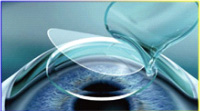

4、取出微透镜完成手术 1、飞秒激光制作透镜和角膜瓣

1、飞秒激光制作透镜和角膜瓣 2、掀开角膜瓣

2、掀开角膜瓣 3、取出微透镜

3、取出微透镜 4、复位角膜瓣 完成手术